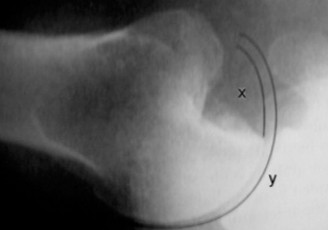

The Axillary View is the absolute gold standard and most crucial radiograph for confirming the direction of any glenohumeral dislocation. In this case, it unequivocally depicted the humeral head resting completely anterior to the glenoid vault. Furthermore, this view allowed for a preliminary assessment of significant anterior glenoid bone loss and a massive, deep Hill-Sachs defect on the posterolateral humeral head, which was actively engaging the anterior glenoid rim.

2. Hill-Sachs Defect: A massive, deep, and wide Hill-Sachs lesion was identified on the posterolateral aspect of the humeral head. Measuring the volume and orientation of this defect confirmed it was an "engaging" lesion.

3. Glenoid Track Paradigm: Applying the glenoid track concept, the massive Hill-Sachs lesion was entirely "off-track." The width of the Hill-Sachs defect far exceeded the remaining intact anterior glenoid articular surface, explaining the absolute mechanical block to external rotation and the impossibility of maintaining a stable closed reduction.